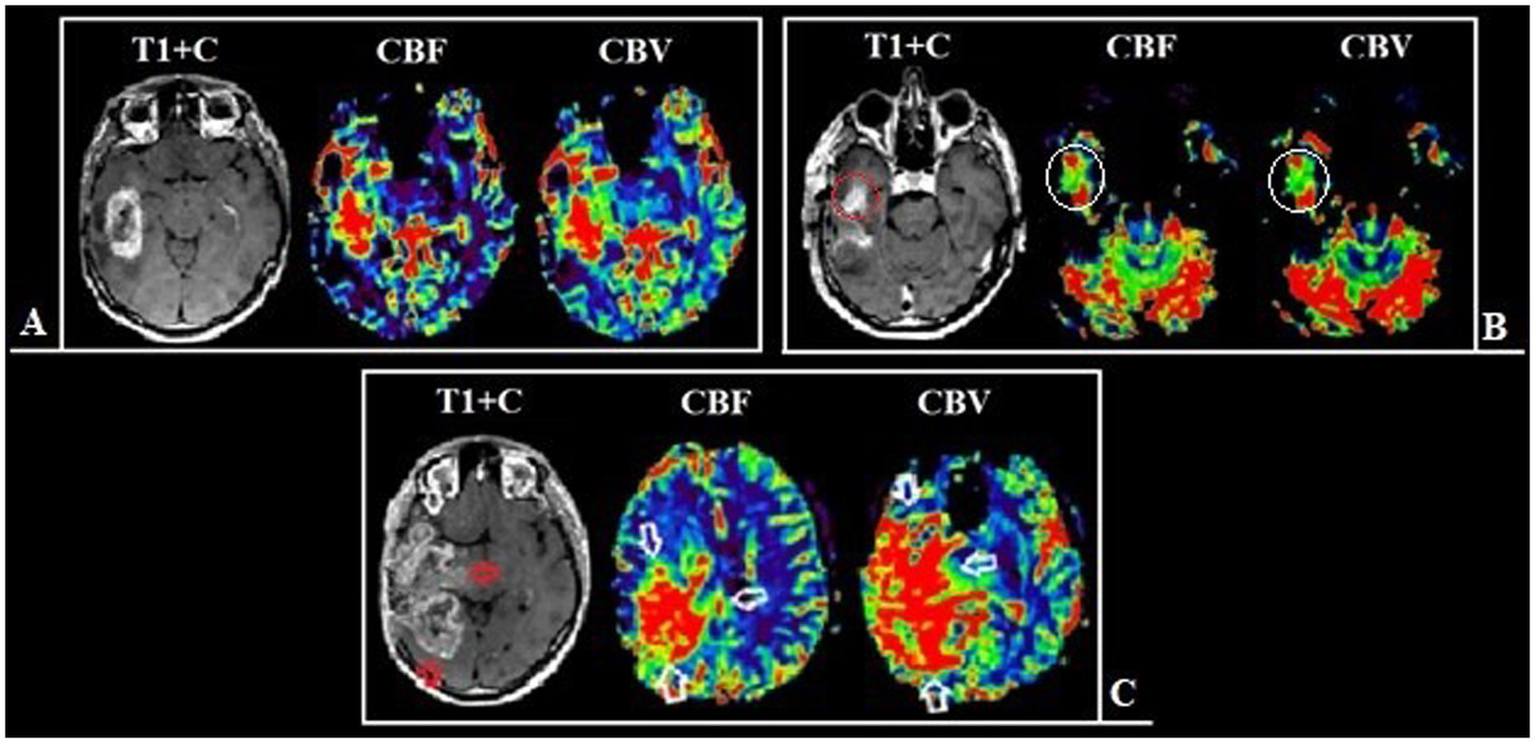

DSC-T2* perfusion was performed in all 74 patients and additional CT perfusion was carried out in 23 of 74 patients. The limitations associated with artifacts from blood degradation products are shown in Figure 2.

Figure 2

Patient T., 42 y.o., left occipital lobe glioblastoma. (A) Post-contrast T1 WI and DSC-T2* perfusion. DSC-T2* perfusion demonstrates marked magnetic susceptibility artifacts with local signal loss due to blood degradation products. (В) CT with contrast (arterial phase) and CT-perfusion. CT-perfusion does not contain any artifacts and fully displays the tumor boundaries.

We identified statistically significant differences in the duration of the relapse-free period depending on the residual tumor volume in the observed groups (p < 0.001). At the same time, the impact was exerted not only by the residual volume of the contrast-enhancing component but also by the residual volume of the hyperperfused tumor part (Figures 5–7).

Patient N., 36-year-old, with a frontal lobes glioblastoma from group 1. (A) Preoperative MRI, post-contrast T1 series and CT-perfusion with CBF and CBV assessment: a tumor with characteristic “butterfly-like” contrast enhancement and central zone necrosis. The perfusion maps demonstrate high values of CBF and CBV both in the contrast-enhanced part and in the perifocal zone that does not accumulate contrast. (B) Postoperative MRI after 24 h, post-contrast T1 series, CBF and CBV obtainer using DSC-T2* perfusion, revealing resection of the contrast-accumulating compound and the compound with high CBV values. (C) Follow-up MRI 12 months after surgical treatment, post-contrast T1 series, CBF and CBV obtainer using DSC-T2* perfusion, there are no contrast-accumulating areas nor areas with high blood volume.

Figure 6

Patient V., 45-year-old, with a left frontal lobe glioblastoma from group 2. (A) Preoperative MRI, post-contrast T1 series and DSC-T2* perfusion: multifocal tumor with the ring-like contrast enhancement, with solid nodes and necrotic areas. The perfusion maps demonstrate high values of CBF and CBV both in the contrast-enhanced part and in the perifocal part that does not accumulate contrast. (B) Postoperative MRI after 24 h, post-contrast T1 series, CBF and CBV parameters obtained using DSC-T2* perfusion show the hyperperfused area localized along the medial contour of the resection (white circle). (С) Follow-up MRI 6 months after surgical treatment: post-contrast T1 series, CBF and CBV parameters obtained using DSC-T2* perfusion: the tumor progression in the previously identified area, which demonstrated high values of perfusion.

Figure 7

Patient Z., 56-year-old, with a right temporal lobe glioblastoma from group 2. (A) Preoperative MRI, post-contrast T1 series and DSC-T2* perfusion: tumor with the ring-like contrast enhancement and central necrotic area. Analyzing the perfusion maps, high CBF and CBV in contrasted tumor part and in area of edema and infiltration are noted. (B) Postoperative MRI after 24 h show the residual tumor parts along the resection border, which accumulate the contrast material, as well as areas demonstrating high perfusion values (С) Follow-up MRI 3 months after surgical treatment: the tumor show pronounced progression of both the contrast-positive (red arrow) and contrast-negative (white arrow) portions.